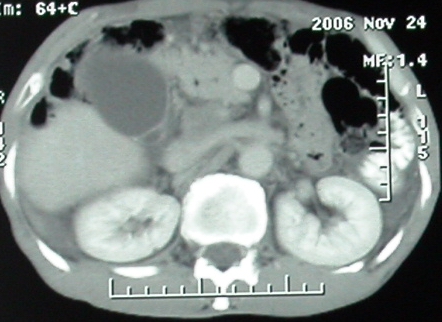

平扫

增强ct所见【动脉增强期】